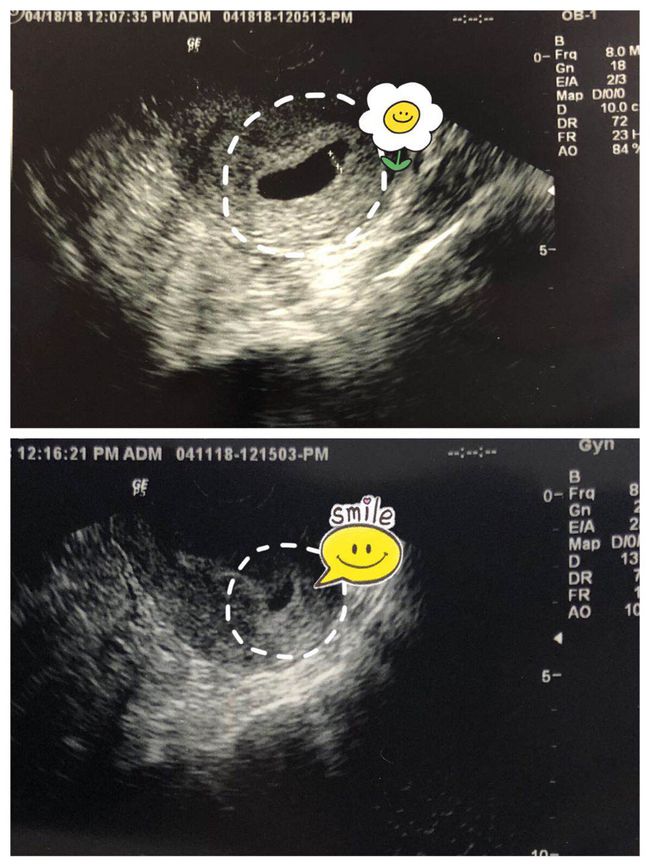

在胎儿发育过程中,定期进行产检是非常必要的。产检可以帮助医生监测胎儿的生长发育情况,及时发现并处理潜在的问题。常见的产检项目包括B超、胎心监护、血常规等。